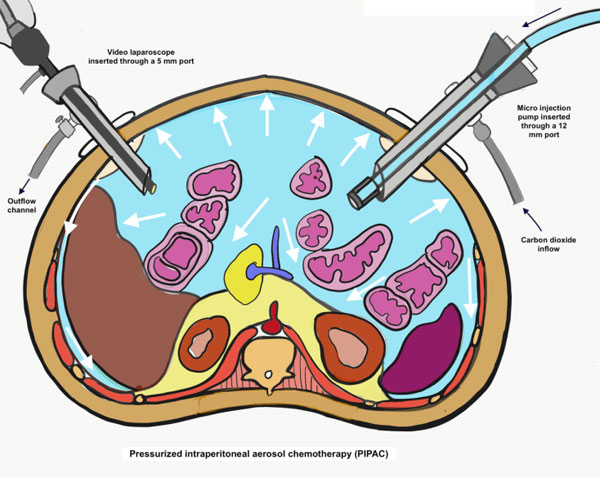

Figure 1: Pressurised intraperitoneal aerosol chemotherapy. A microinjection pump is used to aerosolise the chemotherapy solution that is administered intraperitoneally in the setting of a carbon dioxide pneumoperitoneum maintaining an intra-abdominal pressure of 12mm of Hg for 30 minutes.

Pressurised intraperitoneal chemotherapy, is a new method of intraperitoneal drug delivery. Aerosolised chemotherapy is sprayed in to the peritoneal cavity in the setting of a carbon dioxide pneumoperitoneum- what is known as ‘therapeutic capnoperitoneum’. The technique which was developed by Prof Marc Reymond from Germany, has several advantages over other methods of intraperitoneal chemotherapy. [6]

Instead of distributing the chemotherapeutic substance in the form of a liquid solution into the abdomen, the drug is nebulised with carbon dioxide to create an aerosol. Aerosols consist of two phases: a liquid phase (droplets) and a gaseous phase. According to physical laws, if the size of droplets is small, aerosols behave like a gas. Because a gas distributes homogeneously within a closed space, the drug concentration is expected to be equal within the whole abdominal cavity. Parameters, such as composition, temperature, pressure, and humidity, of the gas are well defined. [6]

As a second difference between PIPAC versus intraperitoneal, the aerosol is applied within the pressurised abdominal cavity so that a pressure gradient is artificially generated between the intraperitoneal and the extra-peritoneal space. As a direct consequence, diffusion of liquids and substances through the peritoneum is enhanced. Moreover, the applied intraperitoneal pressure compensates for the interstitial fluid pressure, which impairs drug uptake into solid tumours and contributes to chemotherapy resistance. [7]

The technique of PIPAC first described by Marc Raymond and collaborators is as follows. A capnoperitoneum of 12mmHg at 37 degrees celsius is created and two balloon trocars are applied.[8] A nebuliser is connected to a high-pressure injector and inserted into the abdomen through a trocar. A pressurised aerosol containing the chemotherapeutic drug is administered. The system is kept in this steady-state for 30 min (application time) and subsequently the aerosol is removed through a closed system. The chemotherapeutic drugs used depend on the primary disease. The procedure is well tolerated and patients are usually discharged the following day. Repeated applications are performed at six to eight week intervals. Before the nebulised chemotherapy is administered, peritoneal biopsies are performed and the peritoneal cancer index (disease extent is evaluated). This provides both a subjective and objective assessment of the response to chemotherapy. [8]